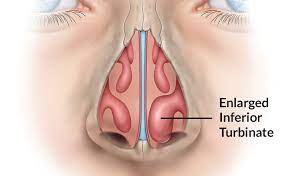

Overview

Package includes:

Days in hospital : 1 to 2 Days (For patient and one attendant)

Days in hotel : 3 Days (For patient and one attendant)

Room type in hospital : Shared

Room type in hotel : Private

Hotel category: Standard

Value added benefits of the Monopolar Cautery Turbinate Reduction:

Ø Doctor consultation charges

Ø Lab tests and diagnostic charges

Ø Room charges inside hospital during the procedure

Ø Surgeon Fee

Ø Nursing charges

Ø Hospital surgery suite charges

Ø Anesthesia charges

Ø Routine medicines and routine consumables (bandages, dressings etc.)

Ø Food and Beverages inside hospital stay for patient and one attendant.

Extra benefits:

ü Interpreter

ü Visa assistance

Ø Site tourism of the city

Ø Follow up with the doctor

Ø Airport pick up and drop

Ø Free online consultation with the doctor

Ø Priority appointments with the doctor

Ø Room upgrade from sharing to private